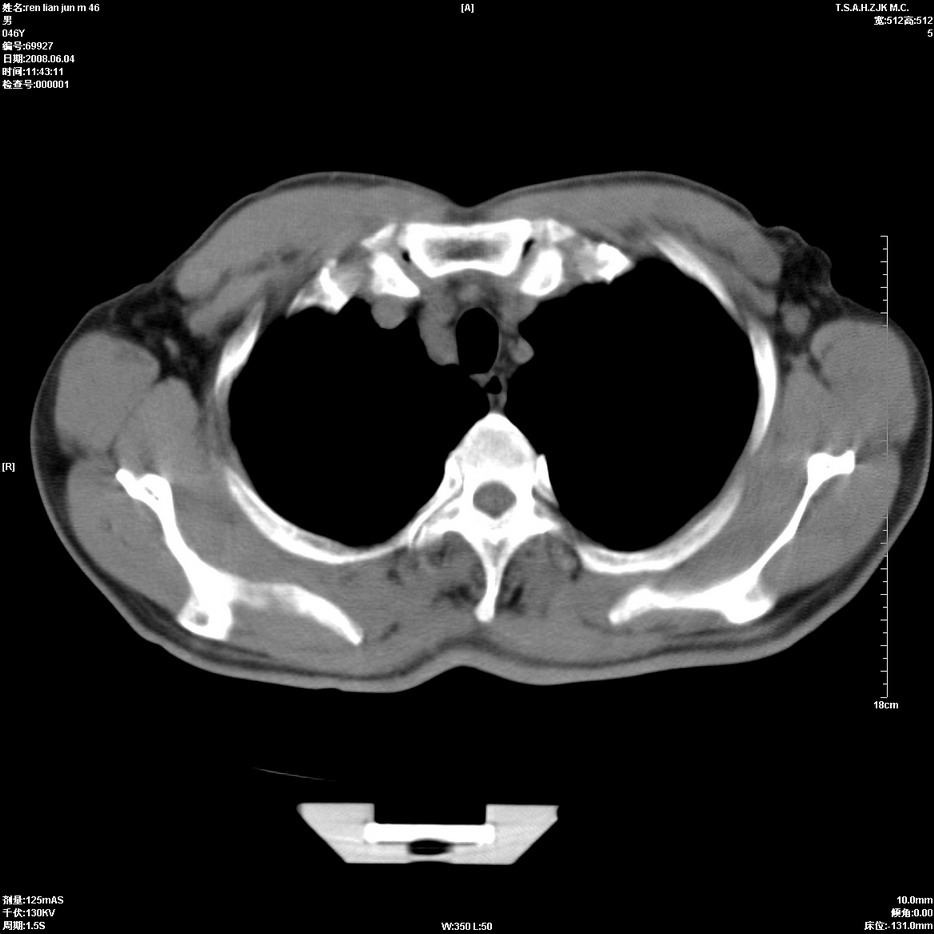

以下是引用qiu999在2008-6-5 17:14:00的发言:[br]考虑右肺中心型肺癌.颅内应做增强检查.

以下是引用形影不离在2008-6-5 19:18:00的发言:[br]右肺中心型肺癌并纵隔及左侧腋窝淋巴结转移,颅内应做增强检查。

以下是引用杀毒软件在2008-6-5 18:33:00的发言:[br]支持考虑右肺中心型肺癌,颅内病变是不是转移,不好说